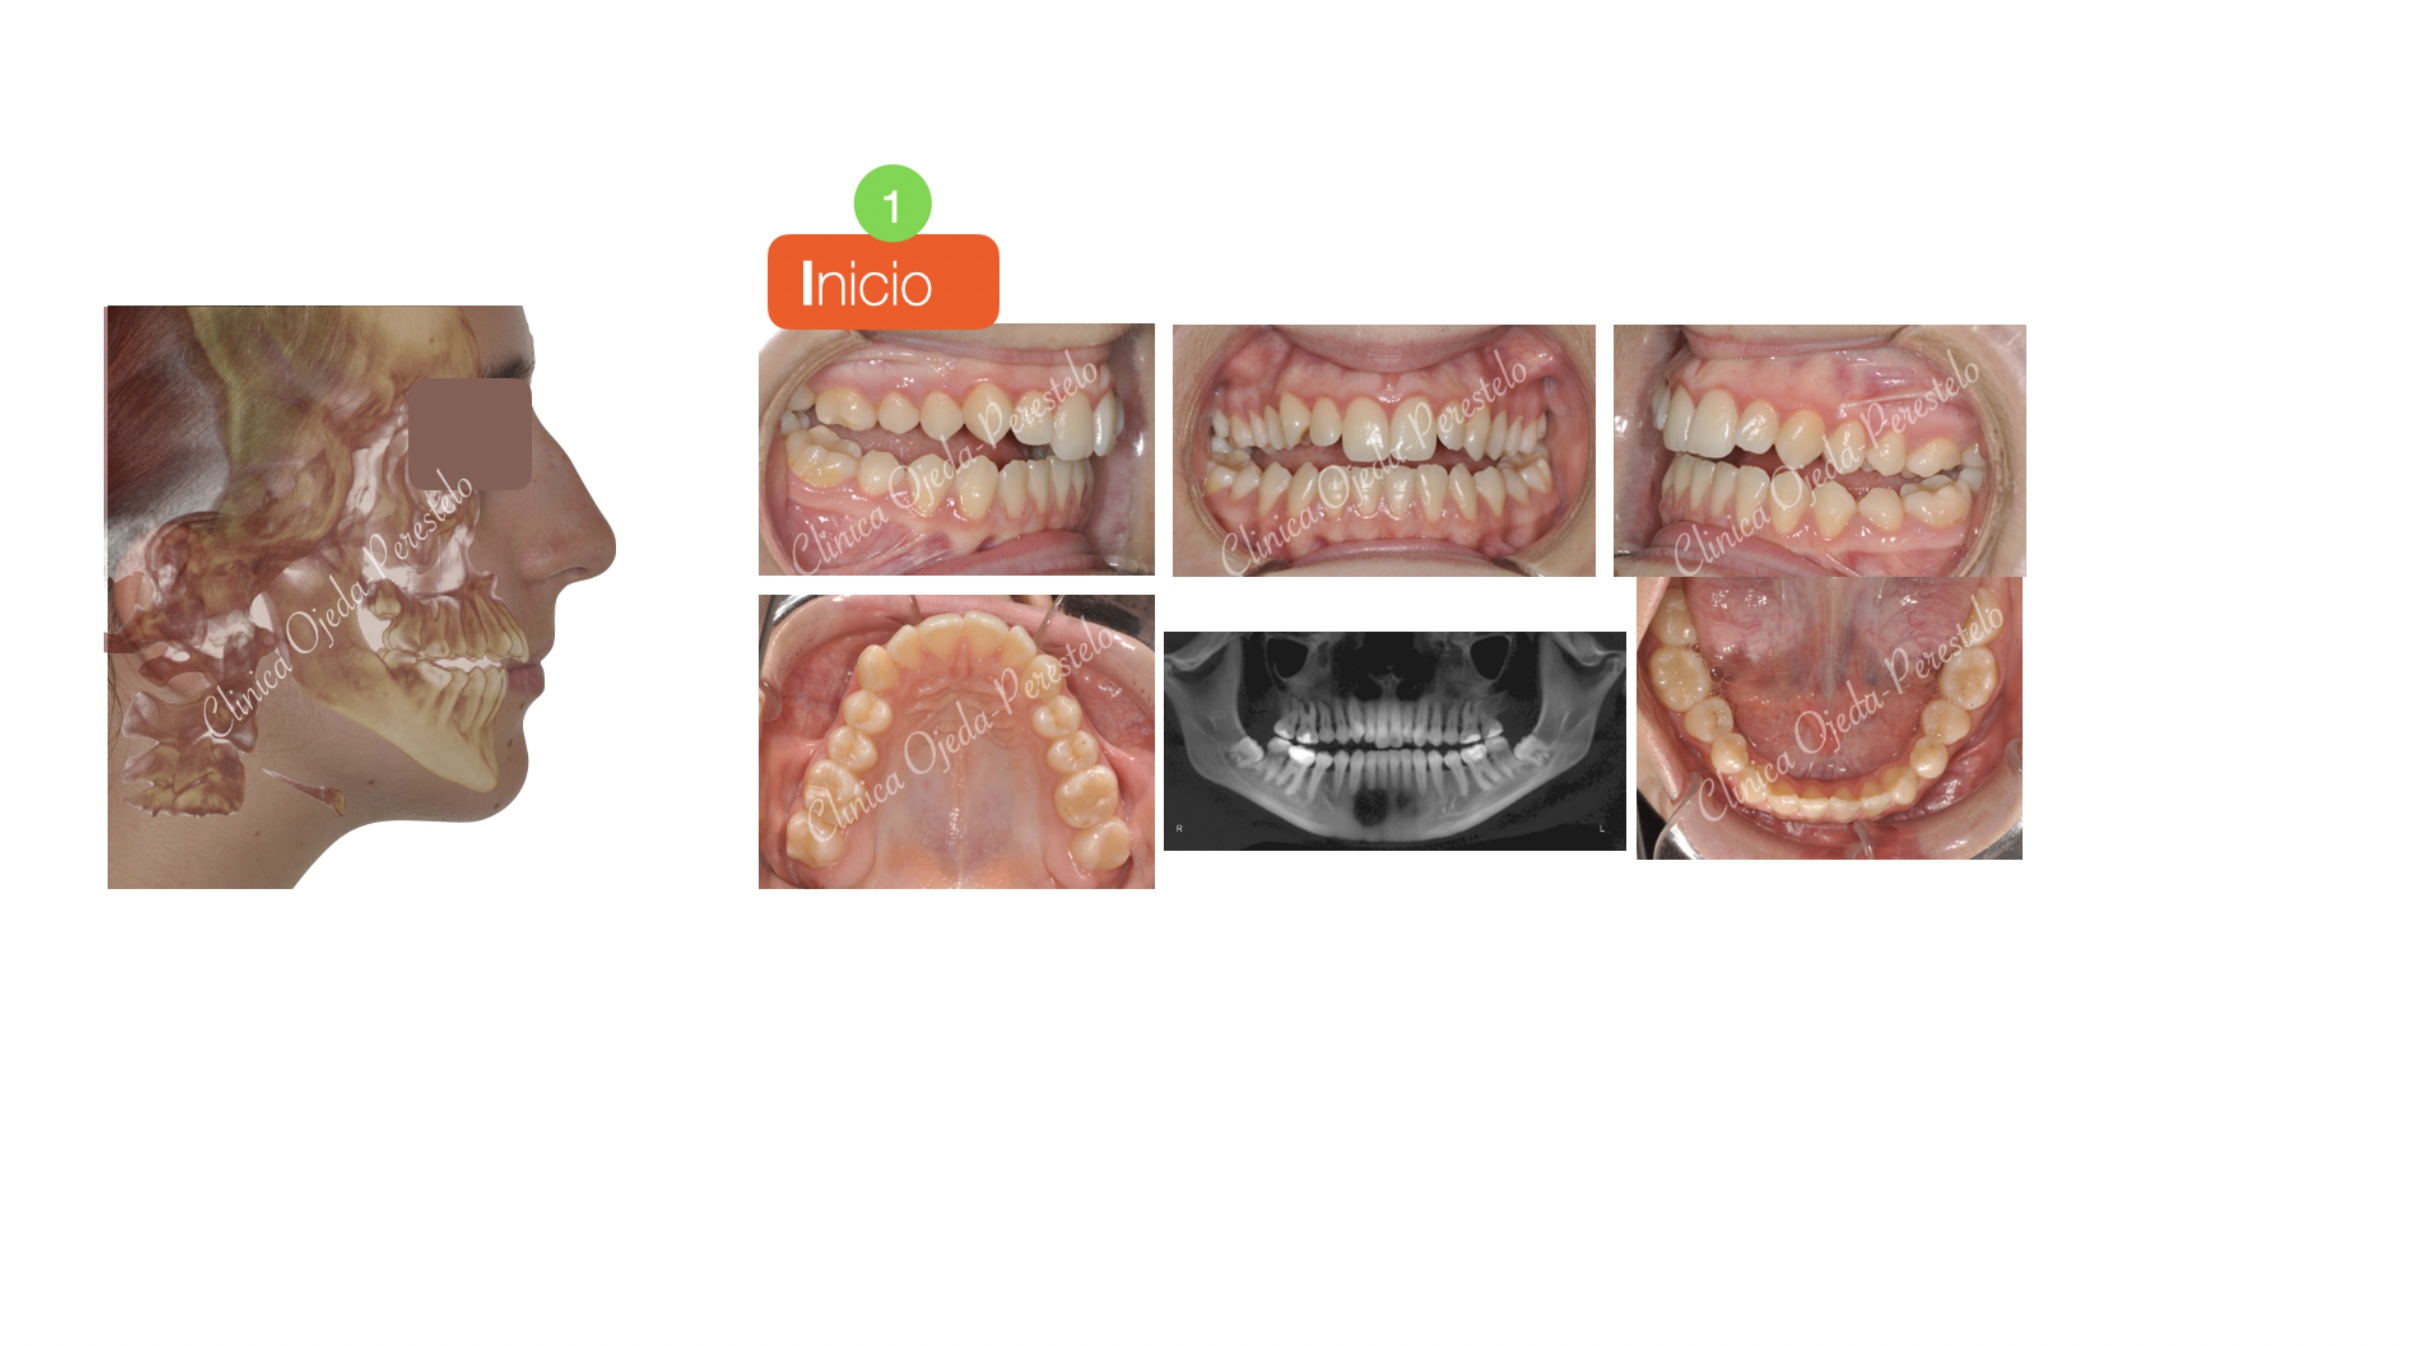

Paciente con problemas masticatorios tratada con Disyunción Oseosoportada (MARPE) y con Microtornillos (2) para el cierre de la Mordida Abierta. Se han alineado y nivelado ambas arcadas con brackets de autoligado pasivo (Sistema Damon) y elásticos intermaxilares.

Quisieramos destacar la amplitud en la sonrisa alcanzada y el gran cierre en la mordida, dotándole a la paciente de una correcta función masticatoria.